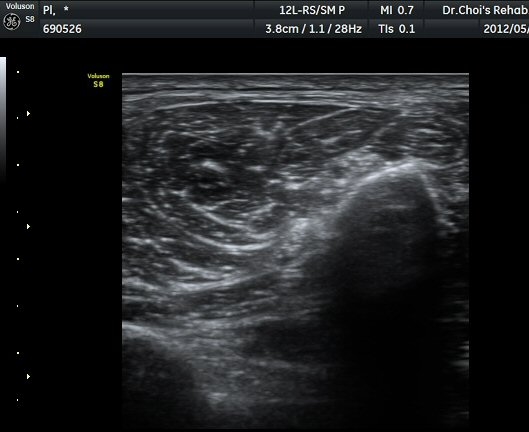

À­´Ù¸®(thigh) ¾Æ·¡ ºÎÀ§ ¿ÜÃø Ⱦ´Ü¸é°Ë»ç¿¡¼­ À̵ιڱ٠³»Ãø¿¡¼­ ÃѺñ°ñ½Å°æÀÌ Á¤»óÀûÀ¸·Î °üÂûµÈ´Ù(±×¸² 1, 2).